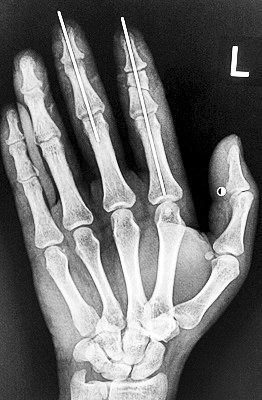

術(shù)后X光顯示,骨骼對位良好。